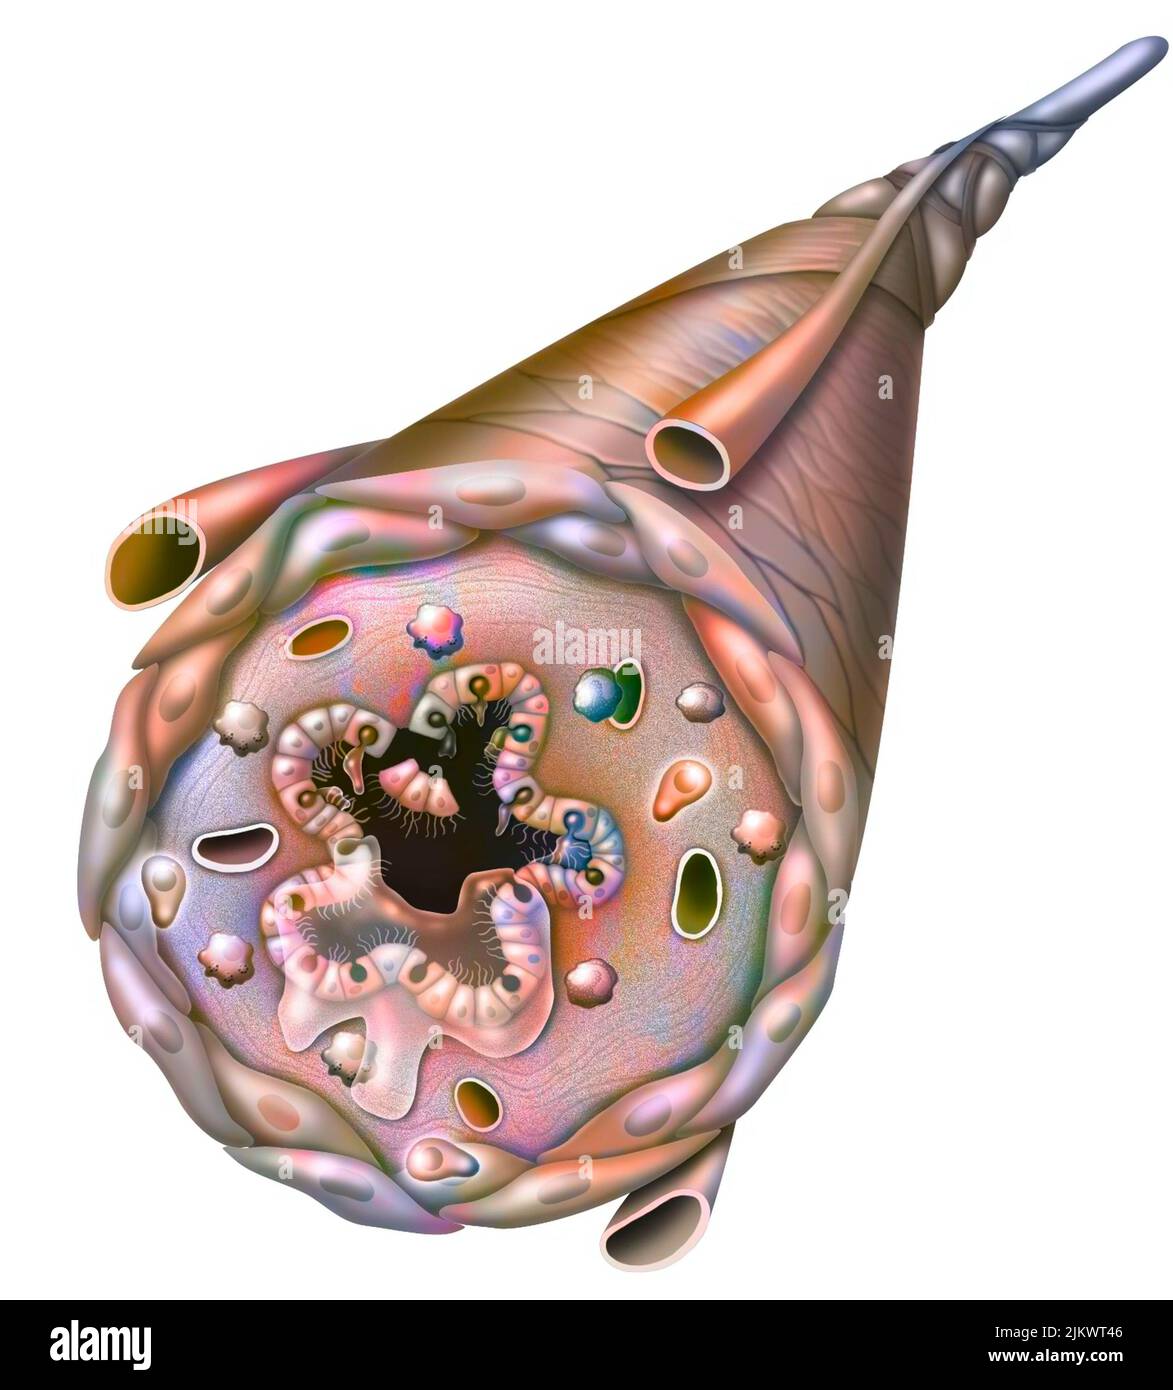

RF2JKWT9A–Oeil, cataracte, phacoémulsification - étape 2: Consiste à casser la lentille avec une sonde.